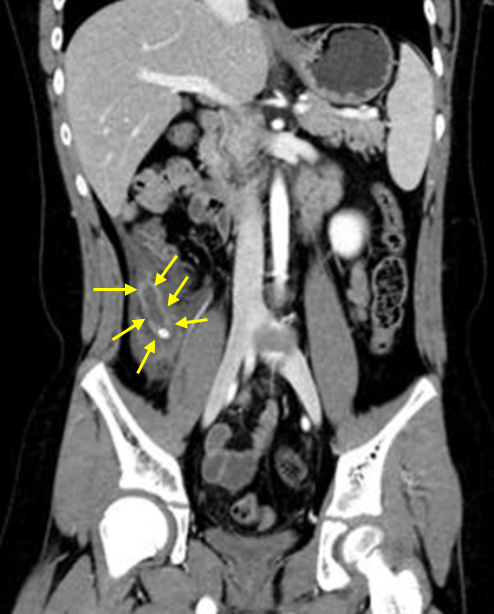

11세 남아가 2일 전부터 배가 아프고 오심이 생겨서 병원에 왔다. 오른쪽 옆구리와 아랫배가 뛸 때마다 아프다고 한다. 혈압 100/60 mmHg, 맥박 90회/분, 호흡 20회/분, 체온 38℃이다. 장음은 감소되어 있고, 오른쪽 아랫배 압통이 있다. 혈액검사 결과는 다음과 같다. 복부 컴퓨터단층촬영 사진이다. 진단은?

Img | CT: Appendiceal enlargement, appendiceal wall thickening, appendicolith |

• 이를 진단하기 위해 시행한 CT상 appendix의 확장과 벽의 비후, 결석을 확인할 수 있다. 따라서 진단명은 급성충수염이다.